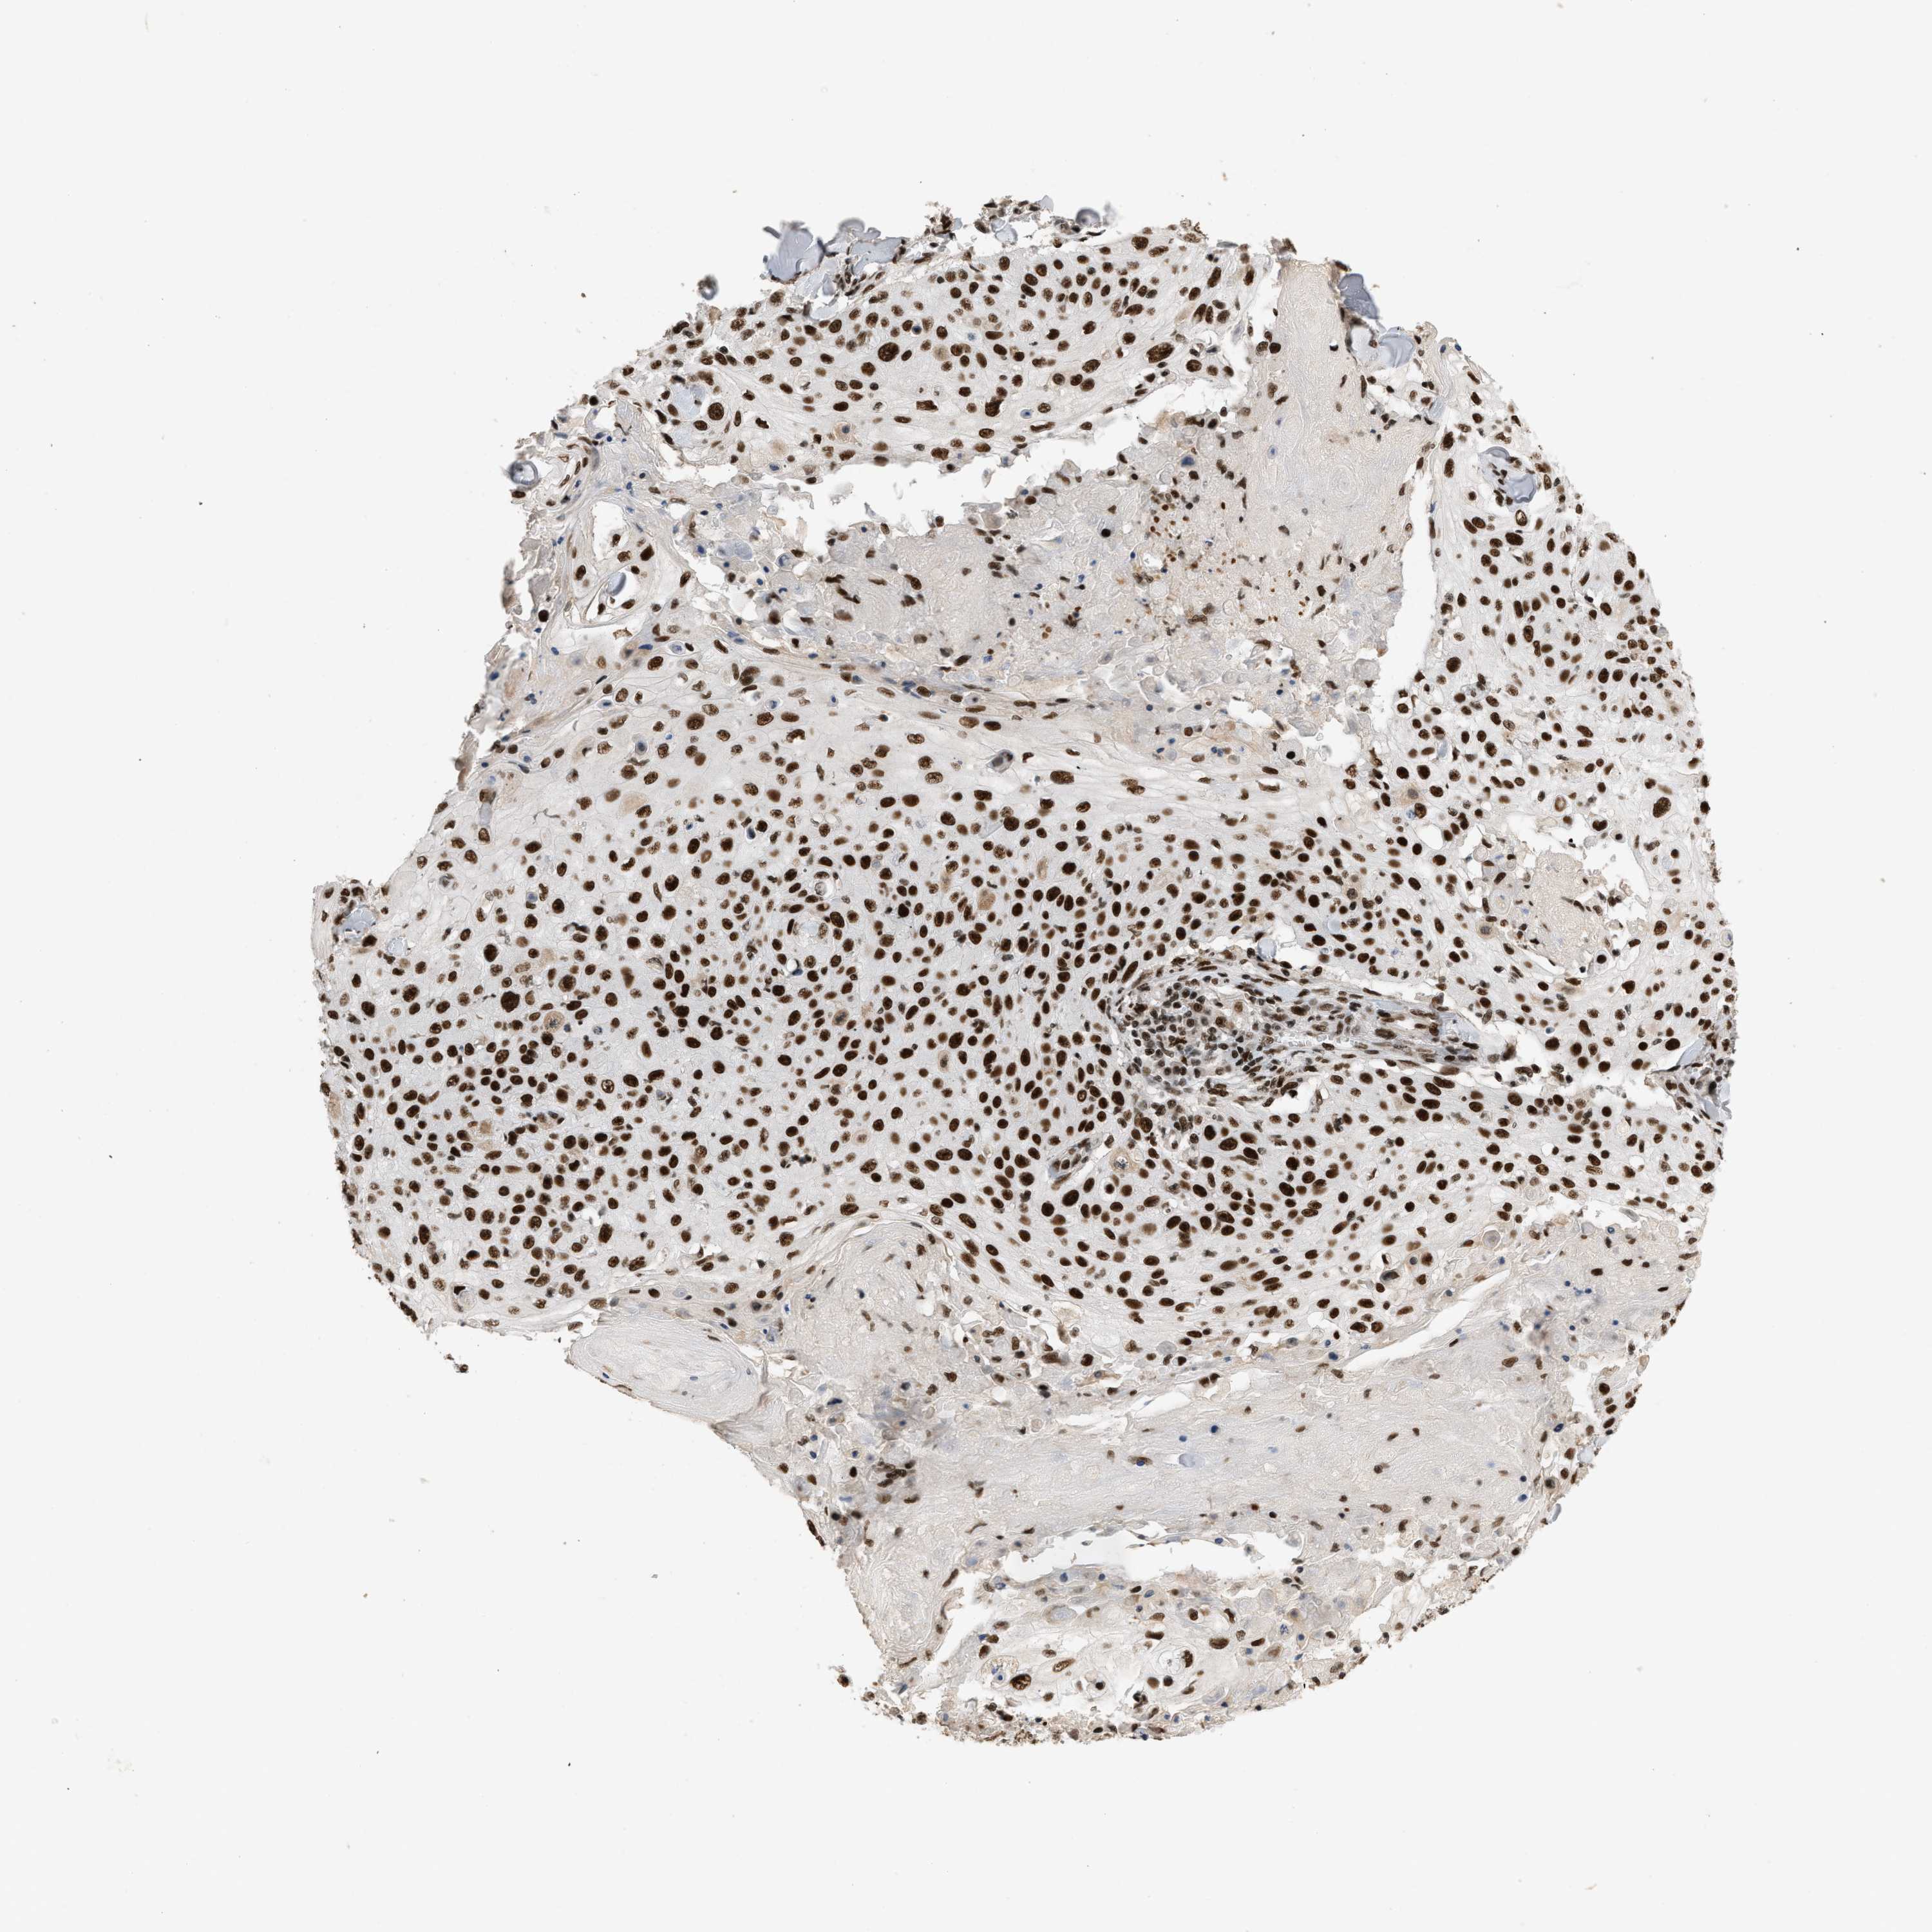

CANCER SKIN CANCER Show tissue menu

Basal cell and squamous cell cancer

SKIN CANCER - Protein expressioni

A mouse-over function shows sample information and annotation data. Click on an image to view it in a full screen mode. Samples can be filtered based on level of antibody staining by selecting one or several of the following categories: high, medium, low and not detected. The assay and annotation is described here.

Antibody stainingi

Antibody staining in the annotated cell types in the current human tissue is reported as not detected, low, medium, or high, based on conventional immunohistochemistry profiling in selected tissues. This score is based on the combination of the staining intensity and fraction of stained cells.

Each image is clickable and will lead to virtual microscopy that enables deeper exploration of all samples and also displays staining intensity scores, fraction scores and subcellular localization as well as patient and tissue information for each sample.

Antibody HPA018248

Staining

High

Medium

Low

Not detected

Intensity

Strong

Moderate

Weak

Negative

Quantity

>75%

75%-25%

<25%

None

Location

Nuclear

Cytoplasmic/membranous

Cytoplasmic/membranous,nuclear

Squamous cell carcinoma in situ, NOS

Squamous cell carcinoma, NOS

Squamous cell carcinoma, metastatic, NOS

Basal cell carcinoma